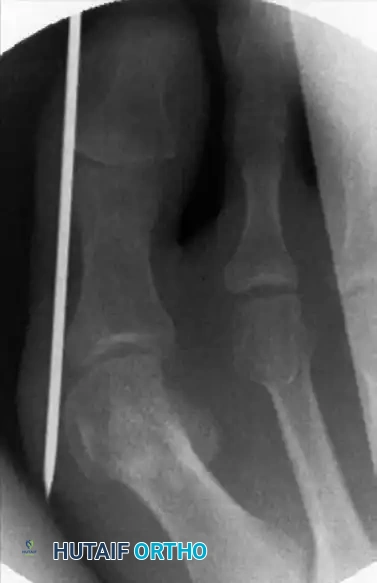

يتم إدخال رأس الجهاز عبر الشق الدقيق إلى العظم. وقبل تشغيل الجهاز، يتأكد الجراح من الموقع الدقيق للقص باستخدام الأشعة السينية المباشرة.

استخدام الأشعة السينية لتحديد موقع القص

أثناء عملية القص، يستخدم الجراح تقنية تبريد مستمرة باستخدام محلول ملحي بارد يضخ مباشرة على العظم. هذا الإجراء حتمي لمنع التلف الحراري للعظم، والذي قد يؤدي إلى فشل التئام العظم أو التهابات خطيرة.

تقنية قص وتعديل العظم بدقة

يقوم الجراح بقص العظم بحركة دائرية دقيقة حتى ينفصل تماما، ثم يتأكد من حرية حركة رأس العظمة تمهيدا لتعديل وضعها.